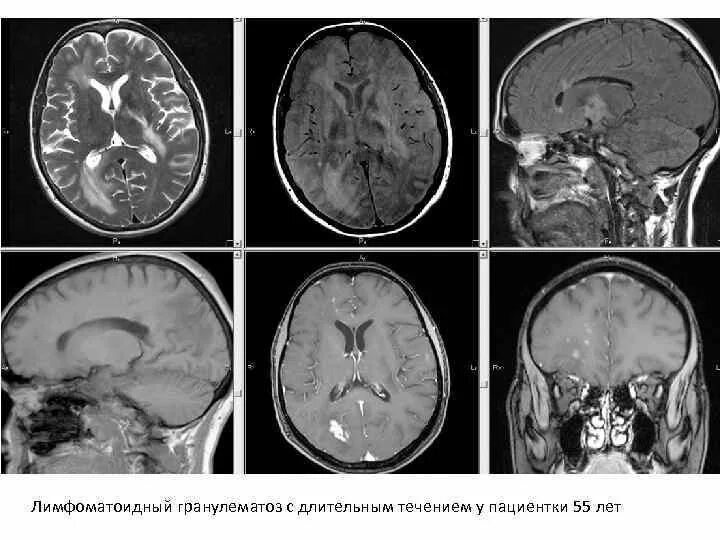

Демиелинизирующее заболевание головного мозга что это такое